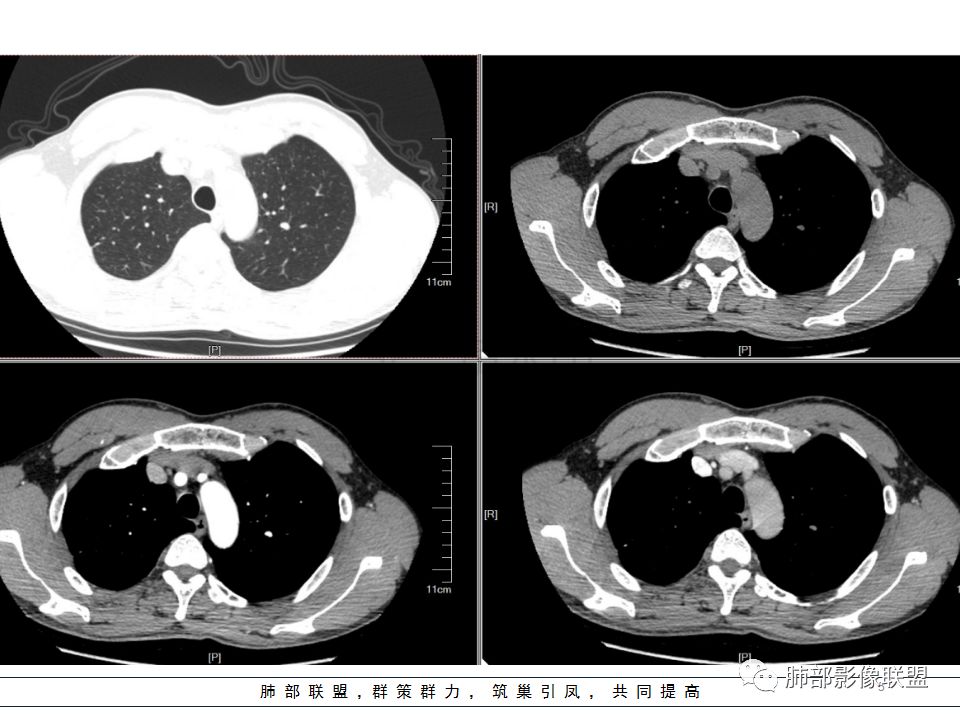

左肺下叶背结节丶融合趋势,形态较单一,平直,无胸膜凹陷,目测轻强化,有支气管爬行丶子灶。诊断:TB>pC>腺癌。

左肺下叶结节,边缘平直为主,部分膨隆,卫星病灶,似乎无强化,糊墙,胸膜下脂肪间隙增宽,结核可能性大,腺癌待排。

左肺下叶背段孤立结节,长轴与胸膜平行,支气管近端截断,刀削平直,糊墙,卫星灶轻强化,考虑TB。

左肺下叶背段小结节 ,糊墙 ,胸膜外脂肪间隙增宽 ,引流支气管壁厚 ,有爬行征 ,病灶无明显强化,考虑结核可能。

考虑结核,左肺下叶病灶,强化不明显,胸膜反应性增厚,有卫星灶,强化不明显。

病史:男,50岁,胸痛15天,无抽烟;胸膜下病灶,有可能相关;

影像:病灶不规则,形态奇特,矢状位可能看到病灶的真实形态;上面近端病灶似乎与主病灶不相连续,多病灶?内侧似乎小花小草,疑为卫星灶;胸膜下病变,与胸膜关系不密切,胸膜线状强化;强化方式渐进性,感觉不均匀,也许是伪影;病灶凹陷平直不膨隆,考虑良性。诊断:结核;鉴别:腺癌(近胸膜端三个胸膜反应凹,偏上部层面毛刺不能除外,但其他地方没有,整体收缩力还比较弱,无钙化,考虑没有形成钙化和纤维化。

男性,胸疼,左肺下叶背段结节,边缘光滑,有平直收缩,轻度延迟强化?胸膜肥厚,有轻度胸膜牵拉,周围有卫星灶,考虑炎性病变,结核,隐球可能性大。鉴别腺癌。

左肺下叶背段结节,边缘较光整,平直,近端支气管未见明确截断征象,沿支气管走行,临近胸膜局限性增厚,增强目测未见明确强化,周围见稀疏小树芽分布,整体考虑良性病变,结核放前考虑。

男,50岁,左肺下叶结节影,似乎两个结节,相邻,上面一个偏内,有分叶,下面一个偏外,胸膜下,内侧有稍增厚的支气管影,并且支气管进入病灶内,周围有更小卫星灶,外侧有胸膜增厚,糊墙。总的来说,考虑炎性病灶,结核可能性最大。但靠内侧的结节有恶性特征,腺癌待排。

50岁男性,吸烟,胸痛15天。左肺下叶胸膜下结节,边缘平直为主,部分膨隆,但似乎呈山丘,沿支气管爬行,周围是卫星灶还是小花小草,考虑恶性,小细胞癌可能性大,结核待排。

左肺下叶背段结节,边缘光滑,有平直收缩,强化不明显,胸膜肥厚,有轻度胸膜牵拉,周围有卫星灶,考虑感染性病变,结核首选。

左肺下叶背段结节,形态近似两个结节融合或靠近,沿支气管走行分布,近侧支气管内见条状软组织,增强未见明确强化,周围见小树芽,首先考虑结核,鉴别小。

患者中年男性,因胸痛半月入院。查血常规、凝血功能、肾功能正常。有抽烟史。胸部CT:左肺下叶背段胸膜下与胸膜垂直长条形不规则病灶,支气管爬行改变,边缘欠清楚,部分层面呈葫芦样见血管集束征、周围点状卫星灶,增强无明显强化,左肺门淋巴结肿大。综合常规结核可能性大,其次小细胞肺癌。鉴别其他。

左肺下叶病变,边缘平直,似有U形凹陷,树芽及卫星病灶,支气管爬行征?无明显强化,考虑结核。

左肺下叶背段近胸膜下结节,部分边缘平直并可见卫星灶,增强后强化不明显,首先考虑结核。

中年男性,左肺下叶背段结节,内可见支气管充气征,周围有晕,周围有结节,局部胸膜增厚,可见脂肪间隙。考虑良性病变可能,隐球?,鉴别结核;病灶有沿支气管生长趋势,气道阻塞,经皮肺穿除外肺癌。

中年男性,胸痛,吸烟史。左肺下叶背段结节,边界清楚,局部见小毛刺及胸膜牵拉,部分层面成葫芦形,局部与胸膜宽基底相贴,邻近胸膜增厚。近端支气管达病灶边缘处,似略增厚。周围见少量卫星微结节及树丫。增强扫描无强化。考虑:1,结核:支持点有发病部位,邻近卫星灶及树丫,近病灶边缘支气管壁似略增厚,邻近胸膜增厚。不支持点,引流支气管壁增厚范围不够长。2,小细胞癌:支持点有局部葫芦形,似沿支气管向肺门区扩展。3,腺癌:支持点有毛刺和胸膜牵拉,当然结核也可以有这两个征象。不支持点有无强化。